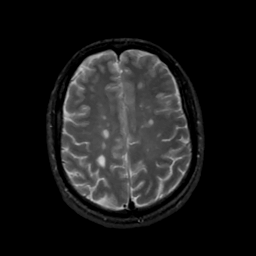

MR Study #15, June 9, 1991 -- Slice #36

[Home][Help][Clinical][Tour 1][Tour 2] Slice 36